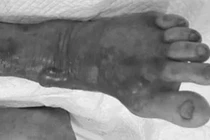

whitmore2.jpg

Chân hoại tử phải cắt lọc do Whitmore - Ảnh BVCC